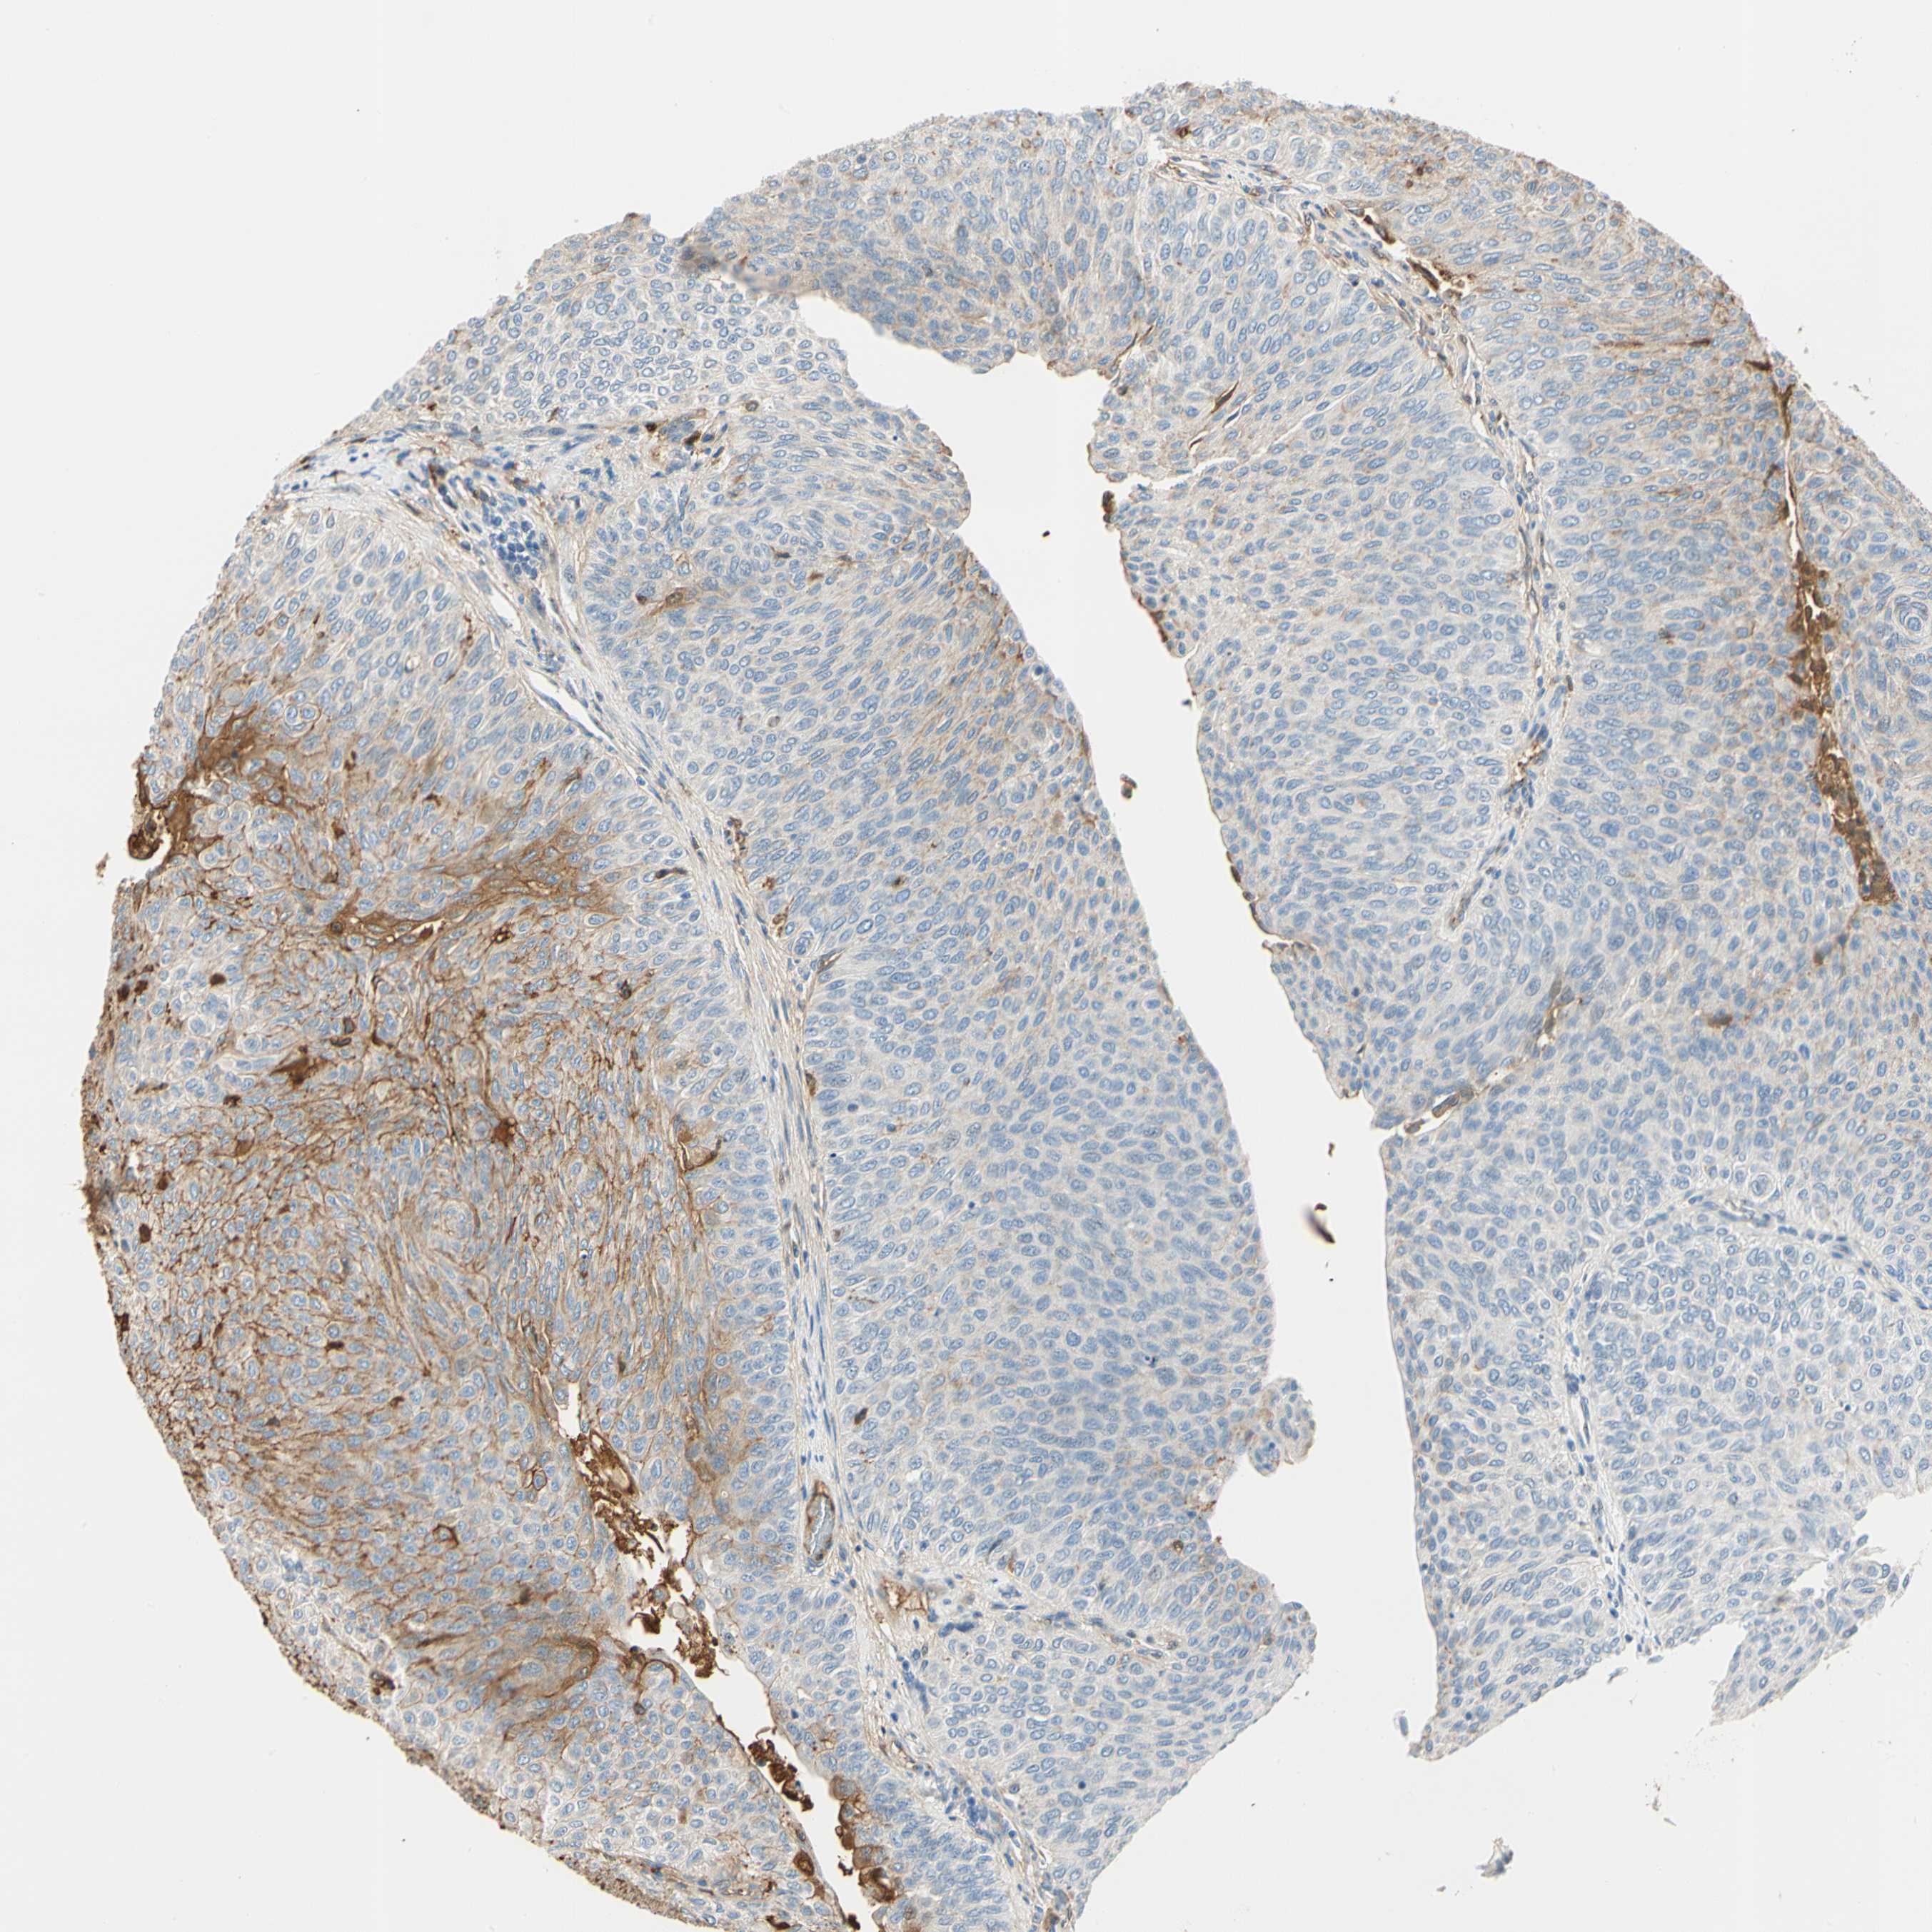

UROTHELIAL CANCER - Protein expressioni

A mouse-over function shows sample information and annotation data. Click on an image to view it in a full screen mode. Samples can be filtered based on level of antibody staining by selecting one or several of the following categories: high, medium, low and not detected. The assay and annotation is described here.

Note that samples used for immunohistochemistry by the Human Protein Atlas do not correspond to samples in the TCGA dataset.

Antibody stainingi

Antibody staining in the annotated cell types in the current human tissue is reported as not detected, low, medium, or high, based on conventional immunohistochemistry profiling in selected tissues. This score is based on the combination of the staining intensity and fraction of stained cells.

Each image is clickable and will lead to virtual microscopy that enables deeper exploration of all samples and also displays staining intensity scores, fraction scores and subcellular localization as well as patient and tissue information for each sample.

Antibody HPA008069

Antibody CAB078183

Staining

High

Medium

Low

Not detected

Intensity

Strong

Moderate

Weak

Negative

Quantity

>75%

75%-25%

<25%

None

Location

Nuclear

Cytoplasmic/membranous

Cytoplasmic/membranous,nuclear

Urothelial carcinoma, Low grade

Urothelial carcinoma, High grade

Urothelial carcinoma, NOS